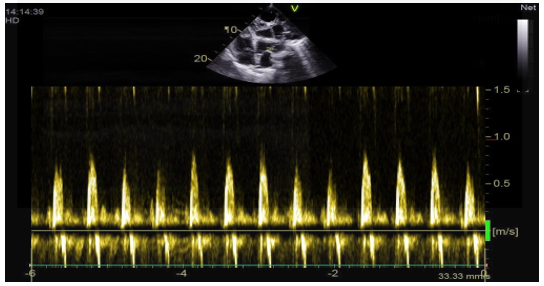

The transthoracic echocardiographic examination revealed (Figures 8 – 18):

- The right ventricle exhibited no dilation (Figure 11) despite the presence of longitudinal systolicdys functio n (Figures 14).

- The inferior vena cavademonstrated no dilation (Figure 18) and wasnoted to be non-compliant (Figure 16).